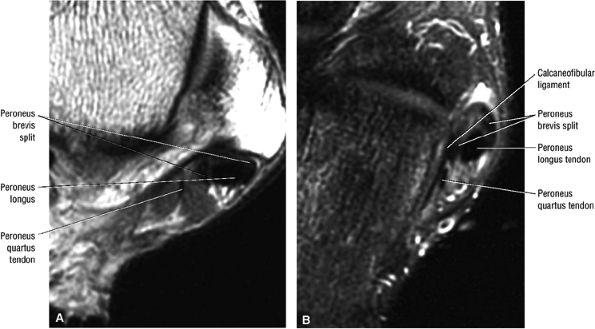

The peroneus quartus muscle is present in 13% to 22% of individuals (Fig. 5.88). This anatomic variant originates from the peroneus brevis muscle and inserts onto the peroneal tubercle of the calcaneus.21